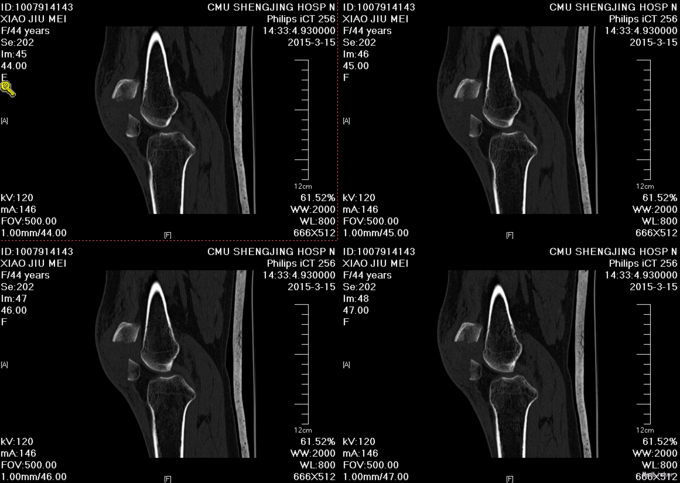

主诉:摔伤后左膝部疼痛肿胀活动受限4小时 患者及家属述患者于2015-3-14日9点40于自家不慎摔倒,导致左膝部疼痛肿胀活动受限,家人急送至沈阳市骨科医院,行DR检查示:左髌骨骨折。未行任何处理,现患者为求进一步诊治来我院,急诊以“左髌骨骨折”为主要诊断收入我科。患者自受伤以来,无发热,无呼吸困难,饮食睡眠正常,二便正常。

诊断:左髌骨骨折 患者入院后见患肢肿胀明显,给予患肢石膏固定抬高位,冷敷,甘露醇消肿等对症治疗,带患肢出现褶皱试验阳性后,CSEA下行左髌骨骨折切口复位张力带内固定术,术后患者肿胀明显,给予,消肿,冷敷,患肢抬高等对症治疗。患者每天换药观察切口愈合情况,无红肿及渗出,待伤口12天后予以拆线治疗,予以出院,给予康复处方。